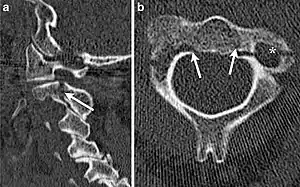

Hangman's fracture is the colloquial name given to a fracture of both pedicles, or pars interarticulares, of the axis vertebra (C2).

The mechanism of the injury is forcible hyperextension of the head, usually with distraction of the neck. Traditionally this would occur during judicial hanging, when the noose was placed below the condemned subject's chin. When the subject was dropped, the head would be forced into hyperextension by the full weight of the body, a sufficient force to cause the fracture. However, despite its long association with judicial hangings, one study of a series of such hangings showed that only a small minority of hangings produced a hangman's fracture.[4]

Although a hangman's fracture is unstable, survival from this fracture is relatively common, as the fracture itself tends to expand the spinal canal at the C2 level. It is not unusual for patients to walk in for treatment and have such a fracture discovered on X-rays. Only if the force of the injury is severe enough that the vertebral body of C2 is severely subluxed from C3 does the spinal cord become crushed, usually between the vertebral body of C3 and the posterior elements of C1 and C2.